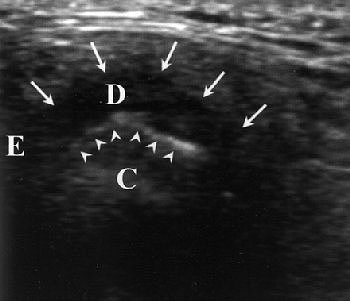

Same patient. Above, sagittal MR image obtained in closed-mouth position shows anterosuperior TMJ compartment and disk (arrows) anterior to condyle. Below, sagittal MR image obtained in maximal open-mouth position shows anterosuperior TMJ compartment and disk (arrows) superior to condyle. Emshoff R, Jank S, Bertram S, Rudisch A, Bodner G, "Disk Displacement of the Temporomandibular Joint: Sonography Versus MRI," (AJR 2002; 178: 1557-1562).